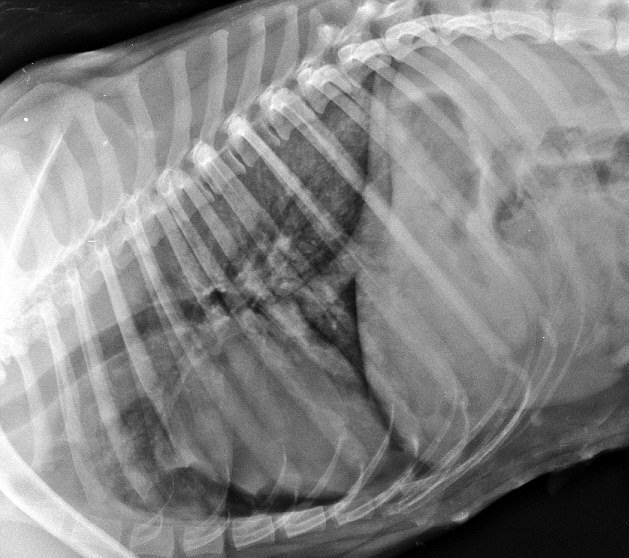

Но она удивительным образом выжила! Да, это просто невероятная история со счастливым концом, приключившаяся на одном из полей Великобритании. В чудесное спасение бордер-колли по кличке Винни с трудом верят даже ветеринары, когда узнают, что по собаке проехал огромный трактор. Более того, она скоро будет рожать! И есть шансы, что щенки будут здоровыми!

Как колли попала под трактор? Собака увидела кролика и буквально сошла с ума, пытаясь его догнать, В итоге и угодила под колесо кормоуборочного комбайна. Спасли ее два обстоятельства: очень широкая покрышка трактора (поэтому давление распределяется равномерно) и очень мягкая земля в тот день, пропитанная влагой. По сути, овчарку просто впечатало в грязь. Но она осталась живой. Правда, были повреждены легкие и сломана тазовая кость.

После пятидневного лечения в ветлечебнице стоимостью около четырех тысяч долларов, овчарку выписали на реабилитацию домой. Специалисты уверяют, что роды должны пройти нормально!